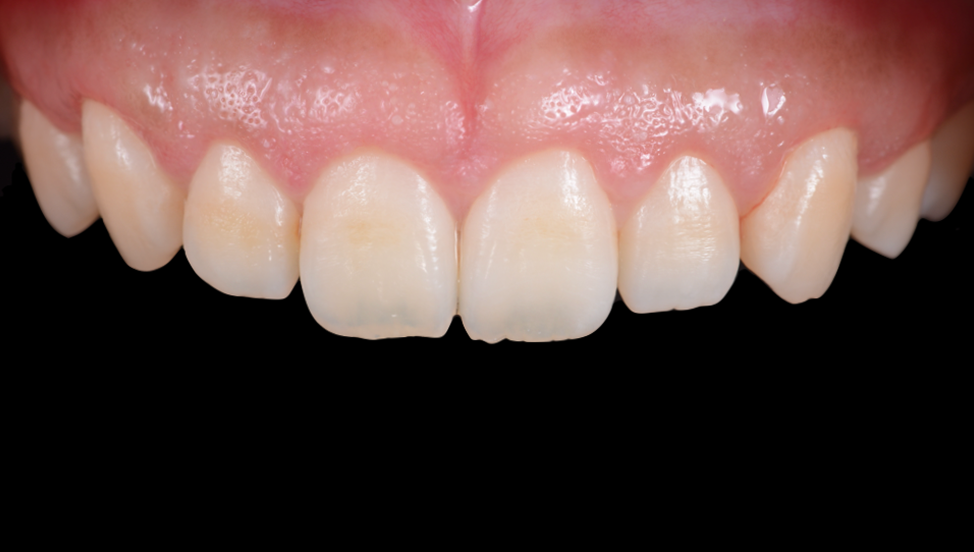

ガミースマイルを歯周形成外科で改善した症例

- 年代、性別 27歳・女性

- 来院動機 ガミースマイルを治したい

- 治療内容 歯周形成外科